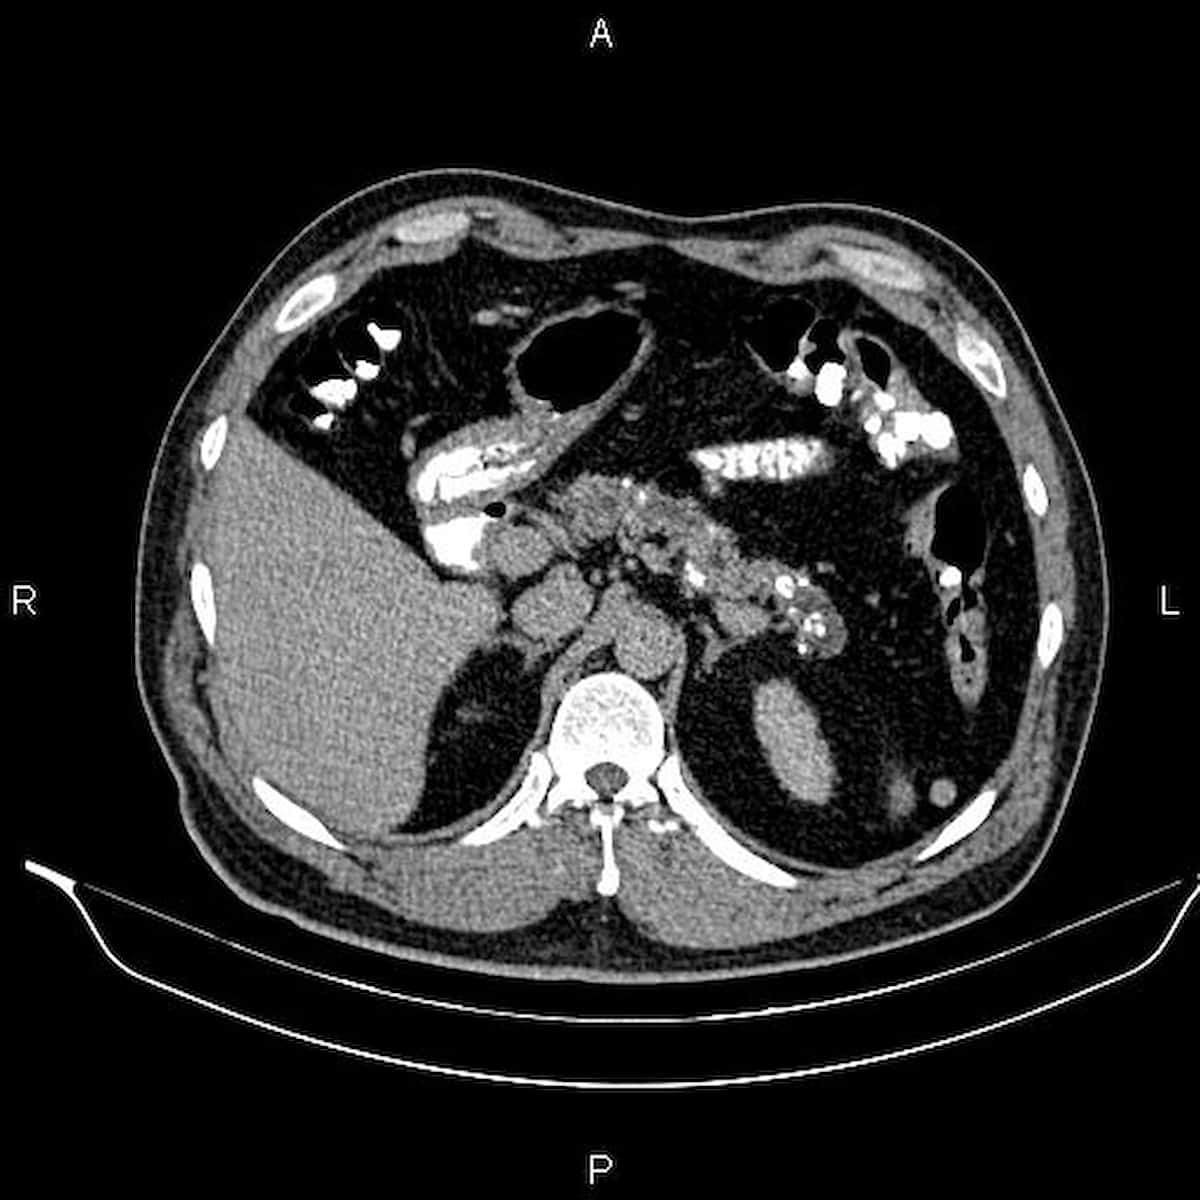

- Le bilan de la pancréatite chronique comprend: bilan hépatique et de malabsorption, scanner abdominal et avis gastro-entérologique

Normale > 250 µg/g (CNPHGE). - Scanner abdominal avec et sans injection